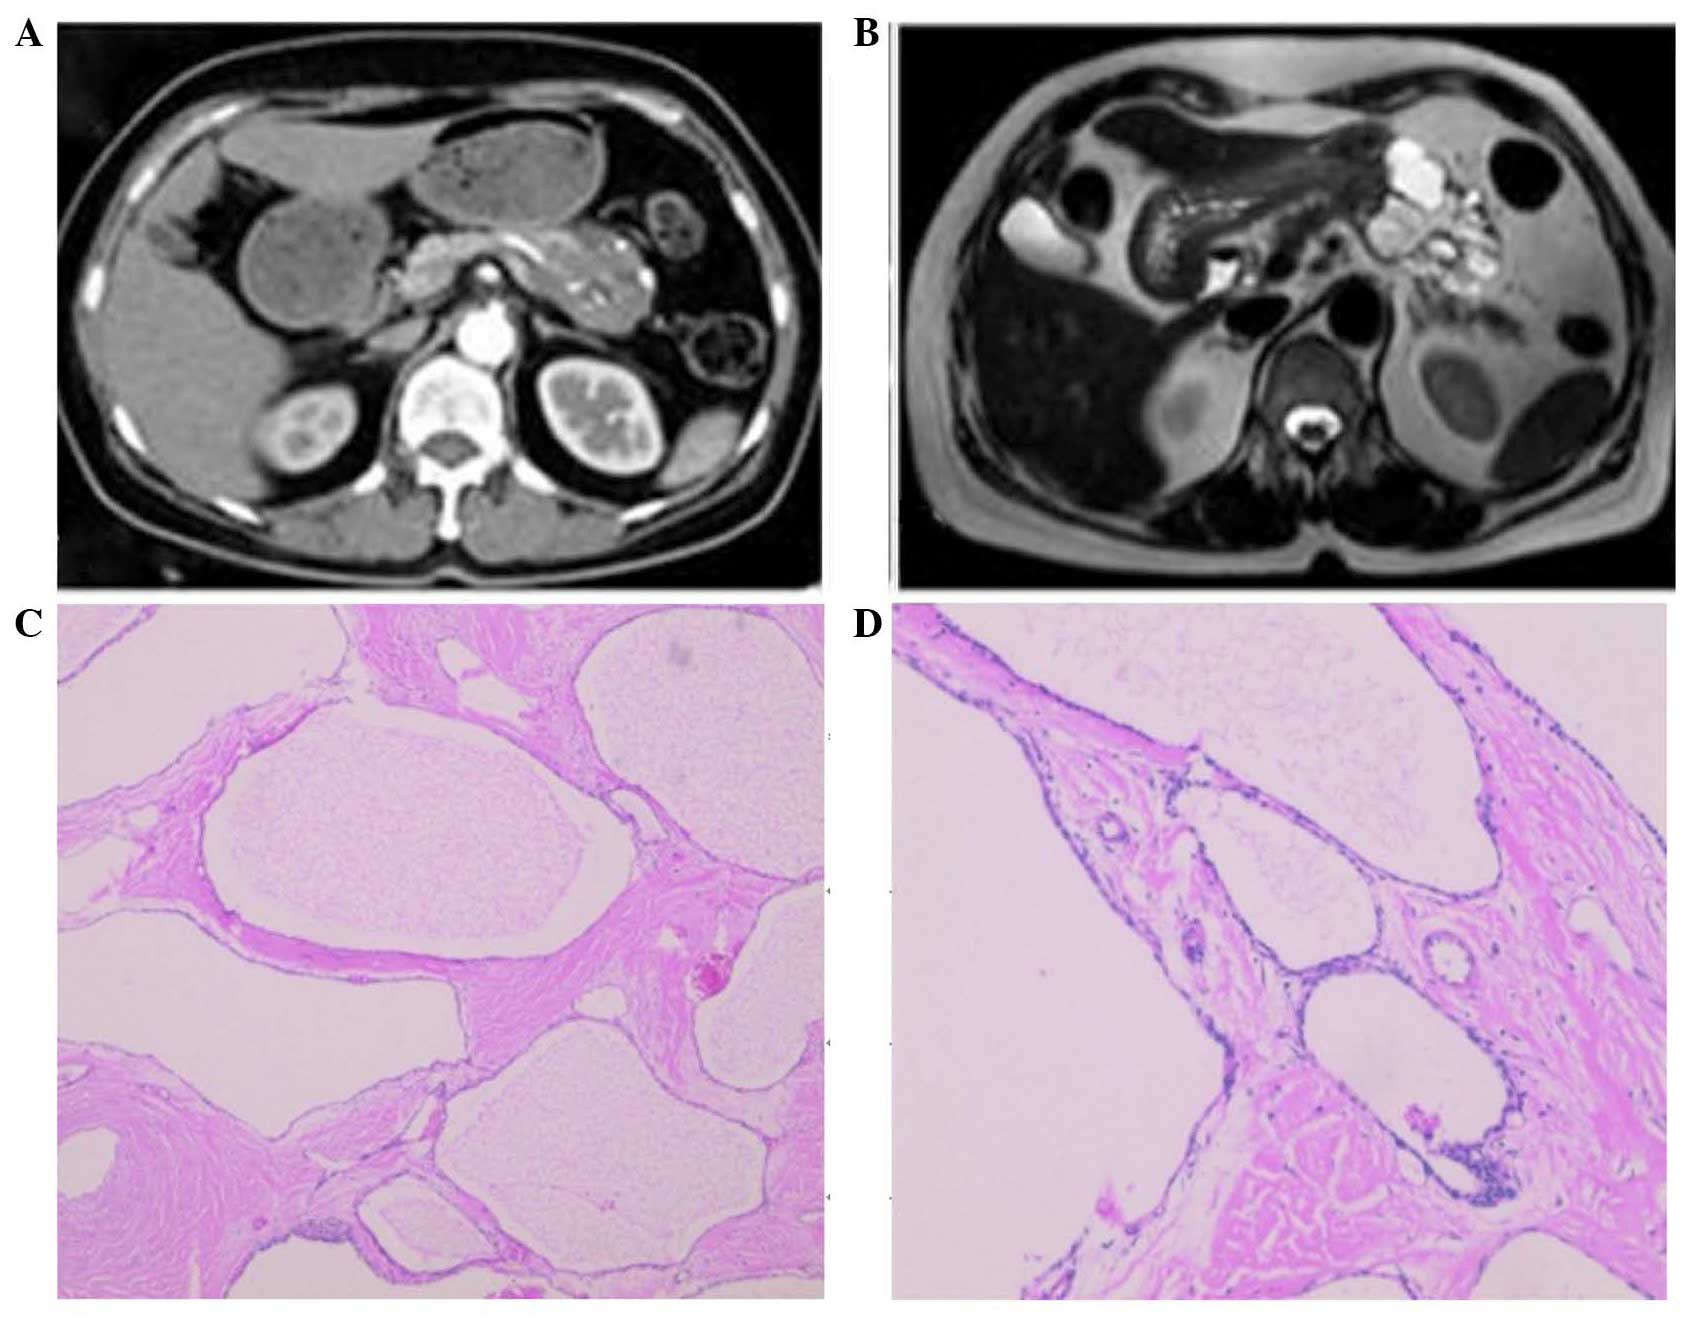

Serous cystadenoma of the pancreas with atypical clinical manifestations: A case report

The present study reported a 4.8 cm space-occupying cystic solid mass of the pancreas, which caused recurrent bilateral lower back discomfort in a 60-year-old female. Combined with the clinical data, an impression of a solid-pseudopapillary neoplasm was generated prior to surgery. Abdominal exploration revealed splenic vessel encasement by the mass similar to the invasion observed in a malignant tumor. Distal pancreatectomy with splenectomy was subsequently performed. Grossly, the tumor was solid and consisted of numerous small cysts. Histopathological examination of the cystic solid mass revealed classic microcystic serous cystadenoma of the pancreas. These findings suggested that microcystic serous cystadenoma can exhibit atypical clinical manifestations. Asymptomatic patients with a small lesion (<4 cm) require imaging surveillance every 2 years; however, tumors >4 cm with atypical presentations require surgical resection.